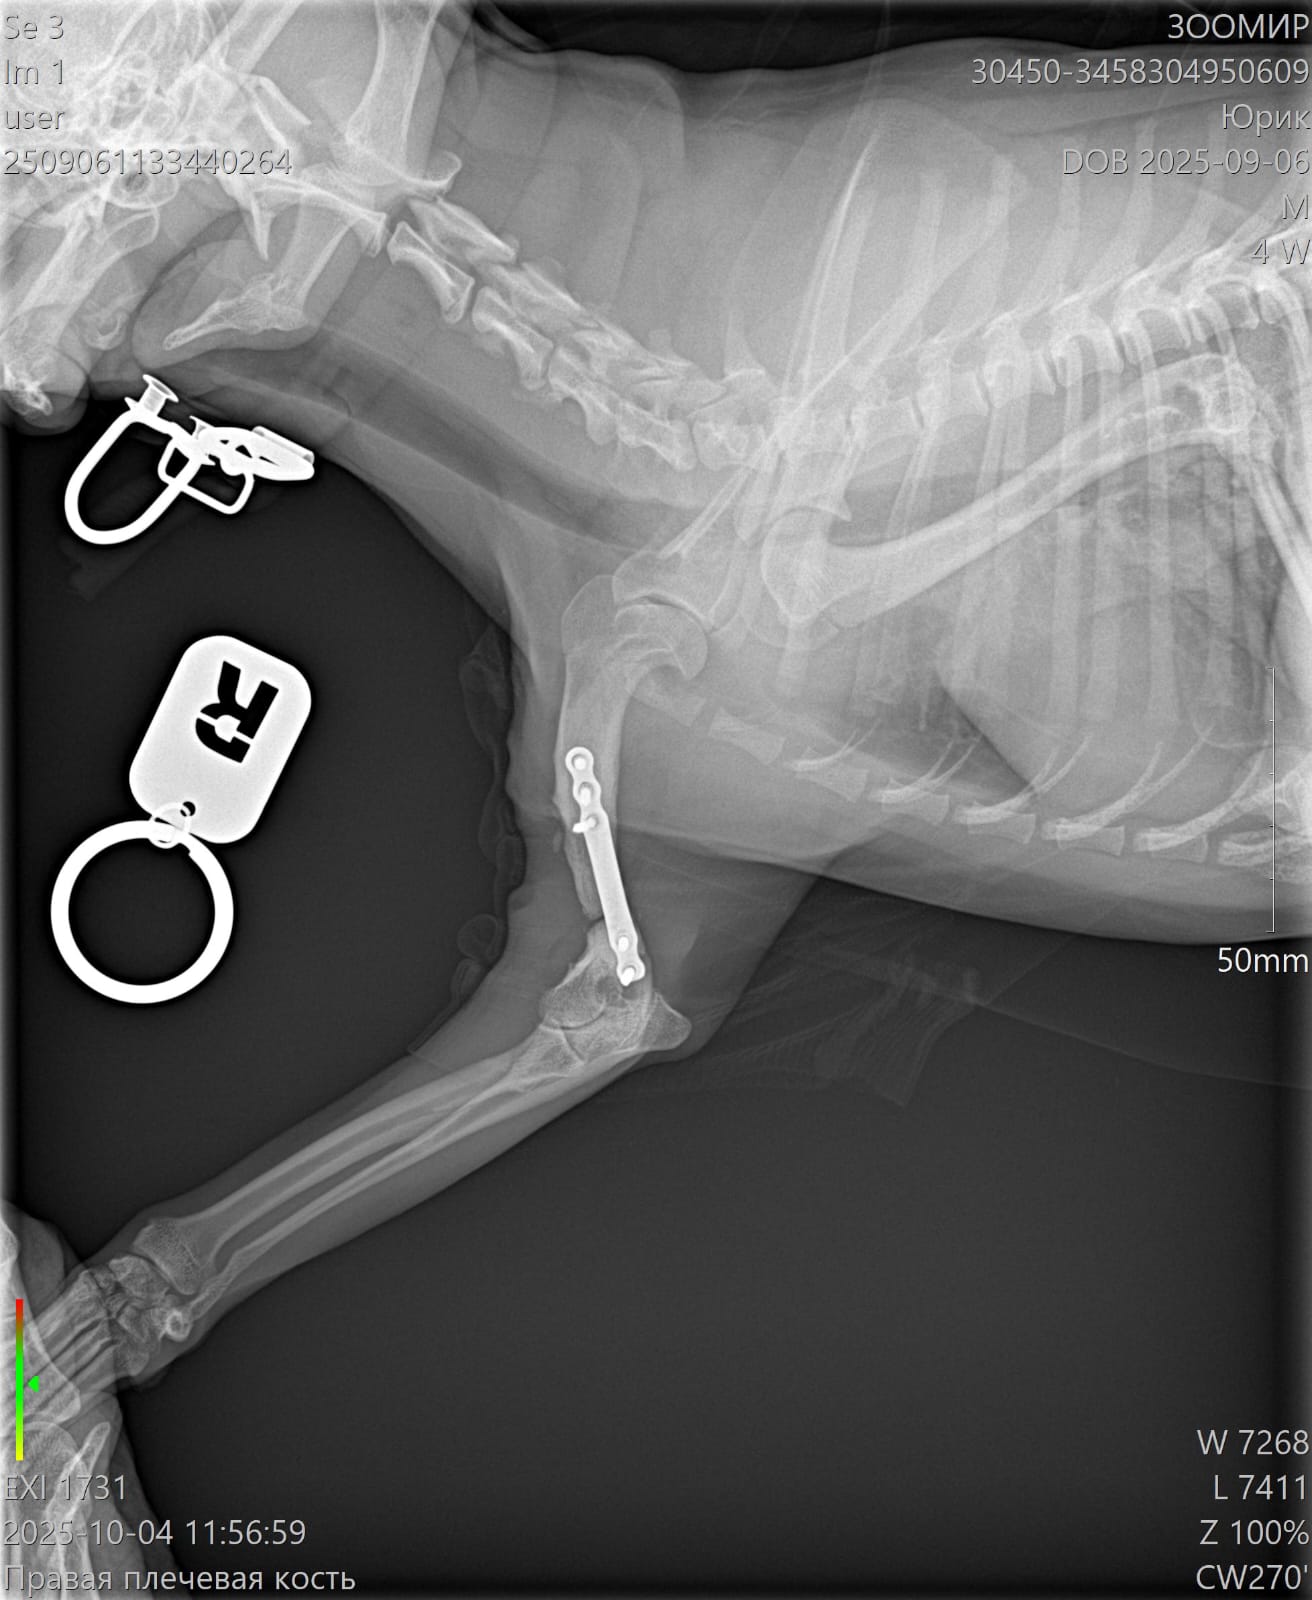

Сделали контрольный рентген - пока мозоли не видно:((((

Лапой на ровном немного пользуется. Но это за счет пластины.

Рентген